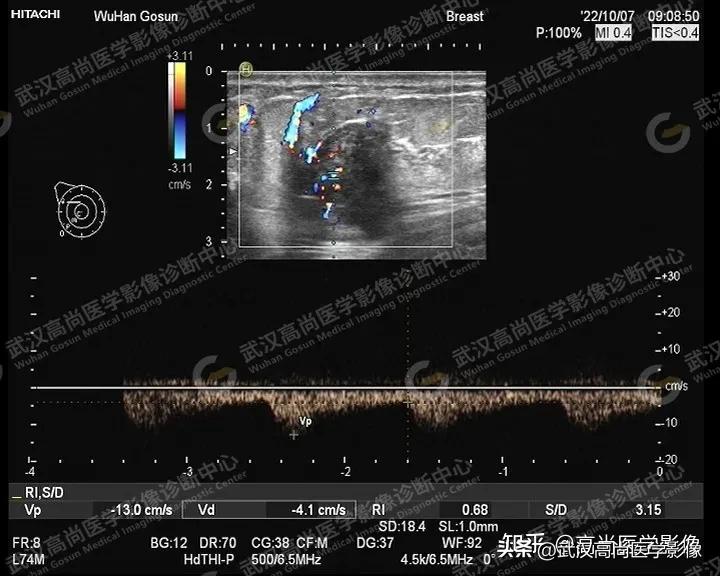

图二

图一、图二、图三:右侧乳腺10点钟方向实性肿块,形态不规则,轮廓不规整,成角,大小约33x24x28mm,内部回声不均匀,内部见散在点状钙化,内血流信号丰富。

图四

图四:肿块内血流信号丰富,RI:0.68。